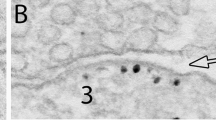

Quantitative electron microscopic methods were used to study possible alterations in presumptive excitatory and inhibitory synaptic circuits in human neocortex removed from patients with intractable temporal lobe epilepsy. Synaptic density was compared between normal and abnormal regions as identified by Nissl staining and immunocytochemistry for the Ca2+-binding protein parvalbumin (PV). The normal regions showed a normal cytoarchitecture and normal pattern of staining for PV, whereas the abnormal regions displayed focal neuronal cell loss and a decrease in immunostaining for PV. In the abnormal regions the overall synaptic density (per 100 μm2 and per mm3) was approximately 30% higher than in normal regions, which corresponded to an increase of approximately 300 million synapses per mm3. The number of excitatory and inhibitory synapses was significantly higher and lower, respectively, than in normal regions. We suggest that these changes are a result of a focal sprouting of excitatory axon terminals and loss of inhibitory terminals which leads to hyperexcitatory synaptic circuits. These circuits may represent a neural substrate for the initiation or propagation of seizure activity in human epileptogenic neocortex.